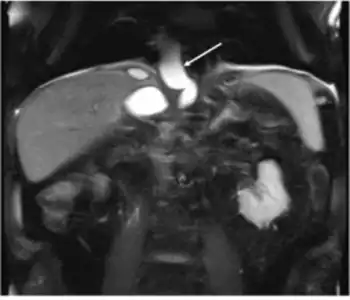

_(1).png.webp)

The most common and effective method of diagnosing a pancreatic pseudocyst is with a CT scan. A pseudocyst generally appears as a fluid-filled mass. In some instances, other methods must be used to distinguish between a normal cyst and a pseudocyst.[3] This is usually accomplished with endoscopic ultrasound or with fine needle aspiration.[2]

Transabdominal ultrasound can be used to identify pseudocysts, which appear on the scan as echoic structures associated with distal acoustic enhancement. They tend to be round and enclosed in a smooth wall. Pseudocysts may appear more complex when young, hemorrhaged, or when complicated due to infection. The transabdominal ultrasound has a sensitivity rate in detection of pancreatic pseusocysts of 75%-90%, making it inferior to a CT scan, which has a rate of 90%-100%.[2]

CT scans are more accurate, and provide more detail regarding the pseudocyst and its surroundings. The CT scan's weakness is its lack of differentiation between pseudocysts and cystic neoplasm. Also, the intravenous contrast given at the time of the CT scan may worsen kidney dysfunction.[2]

MRI and MRCP are effective methods of detecting pseudocysts, but are not regularly used because CT scans offer most of the needed information. These scans do, however, provide better contrast, which allows for better characterization of fluid collections, depicting debris within the collections, and detection of bleeding.[2]